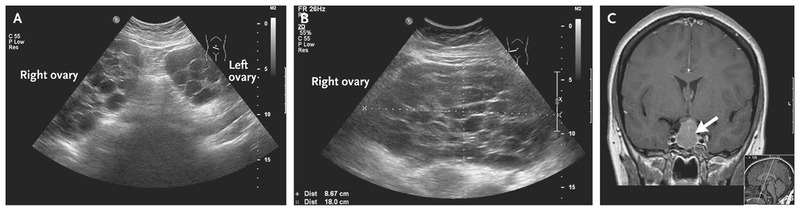

Узи при боли в животе 84 фотографий